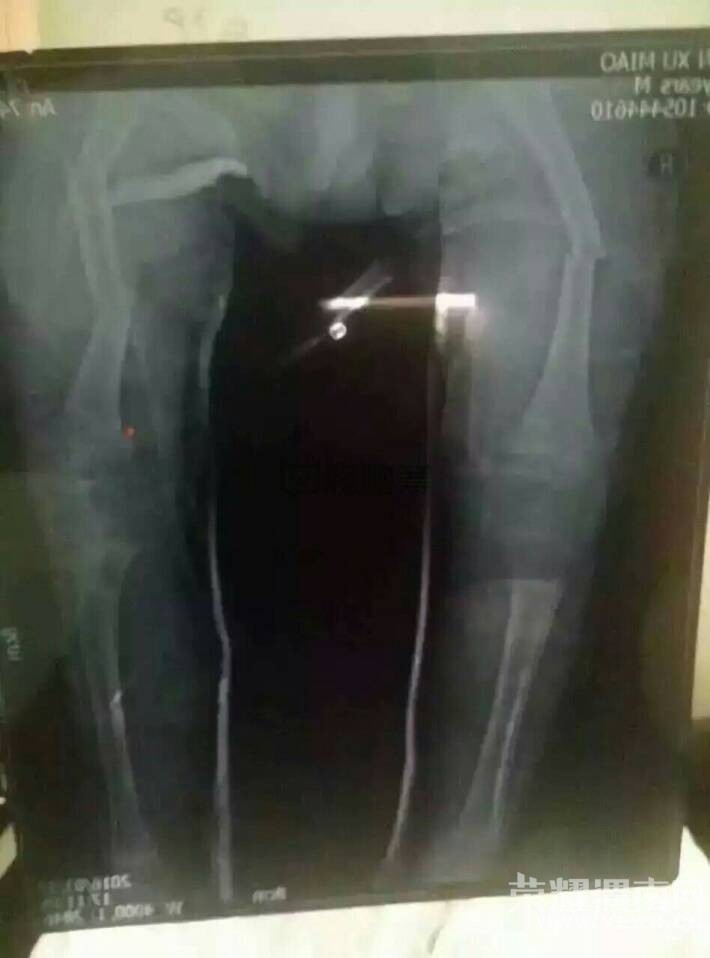

3月27日下午,渭南市临渭区三岁多的留守男童尹旭淼在家由60多岁的爷爷看护,因意外事故,造成孩子左大腿两处骨折,右大腿三处骨折,盆骨粉碎性骨折,一边膝盖骨骨折,尿管断裂。孩子现住西京医院骨科六楼21床,目前已花费15万元,面对接下来的巨额手术费,这个普通的农村家庭已经濒临绝望的边缘。

本人吕莎 我的小外甥 尹旭淼 3岁7个月,家住陕西渭南临渭区 龙背乡程前寸5组,上小班,前几天在家因意外,造成左大腿两处骨折,右大腿三处骨折,盆骨粉碎性骨折,一边膝盖骨骨折,尿管断裂,现住西京医院骨科六楼21床。现西京医院主治骨折,尿管断裂必须转院到上海医治,保守估计30万。家住农村,父母离异,孩子爷爷奶奶均已在65岁以上,孩子爸爸打工支撑家庭生活,可现在庞大的医疗费用使这个农村家庭无法承担,请大家伸出自己的援助之手,为这个小生命献一份爱心,谢谢大家!